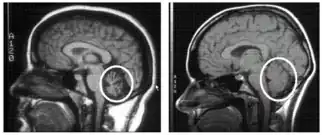

| Cerebellum (labeled bottom right) of the human brain. It is located above the brain stem, posterior to the brain. | |